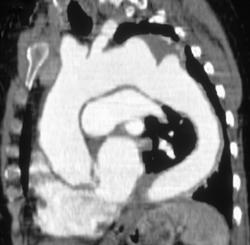

Melanoma Metastatic to Left Hilum